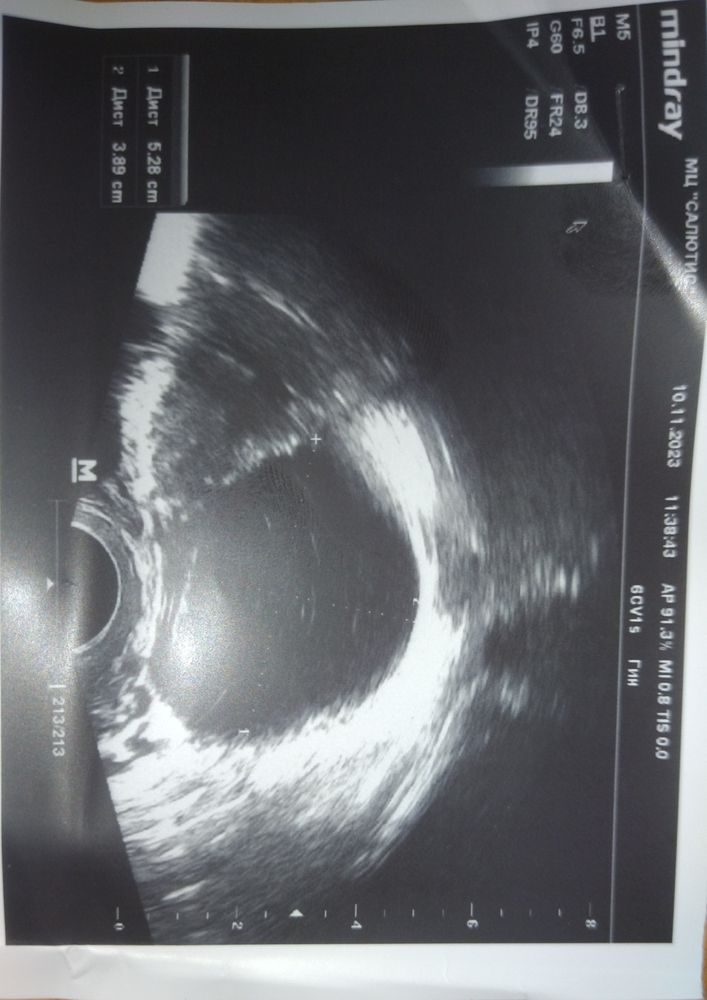

УЗИ. Киста большая

Дарья Х., там под вопросом. Лютеиновая... А может нет. Знаю, что на УЗИ, как закончаться М. Но их ещё дождаться надо)